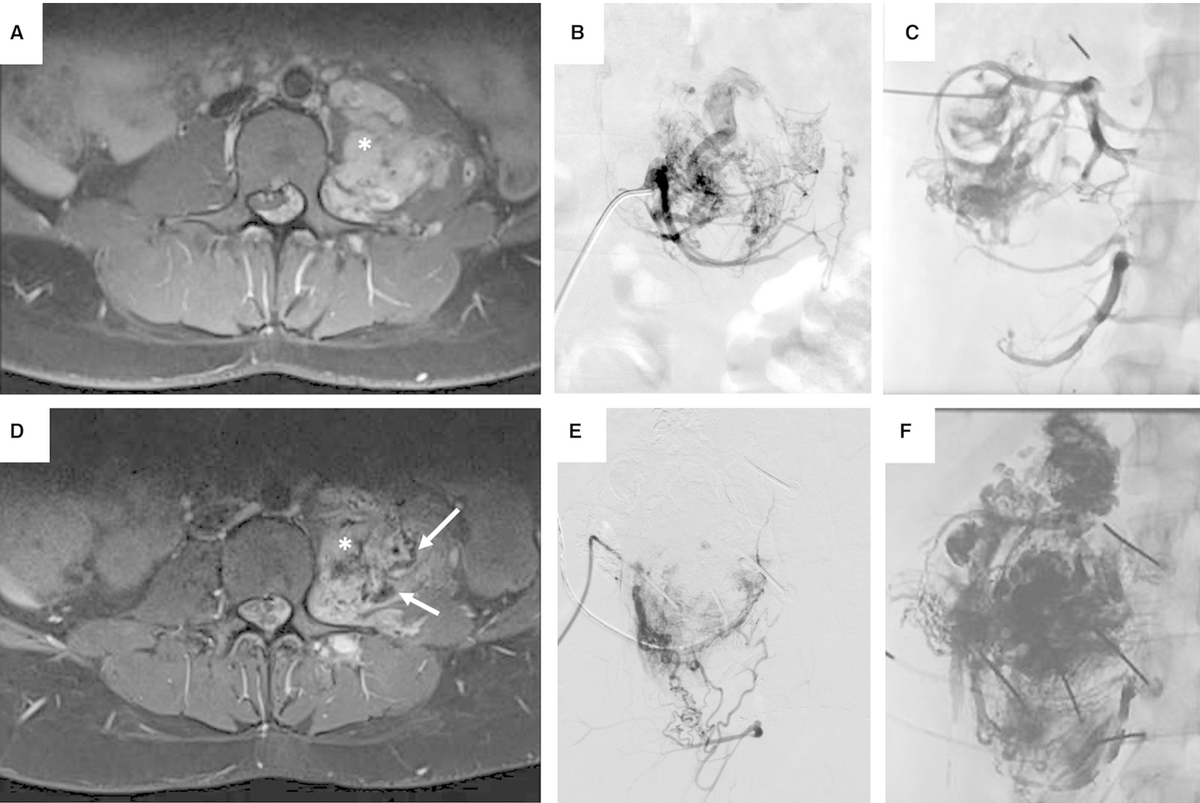

#ThrowbackThursday! Back to 2023 ↩️ Clinical Outcome and Quality of Life of Multimodal Treatment of Extracranial Arteriovenous Malformations: The APOLLON Study Protocol bit.ly/3Wm02EE #OpenAccess 🔓 Vanessa F. Schmidt, MD, MHBA, EDiR

#ThrowbackThursday! Back to 2023 ↩️

Clinical Outcome and Quality of Life of Multimodal Treatment of Extracranial Arteriovenous Malformations: The APOLLON Study Protocol

bit.ly/3Wm02EE

#OpenAccess 🔓

<a href="/VanessaFSchmidt/">Vanessa F. Schmidt, MD, MHBA, EDiR</a>